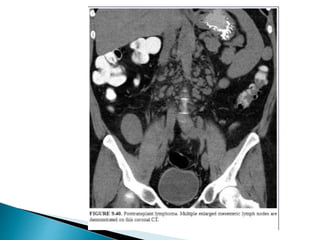

 Increased risk of malignancy in post RT patients.

 Related to the dose and duration of the immunosuppressive

drugs.

1. Lymphoprolefeative disorders(PTLD):- esp in patients with

EBV.

2. Renal cell carcinoma (2 %):- 1oo times increased risk and

most common cell type is Papillary carcinoma.

3. Lymphoma.